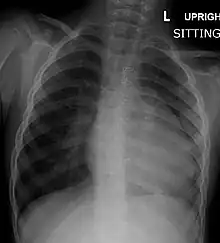

Chest radiograph

Before more sophisticated techniques became available, chest X-ray was the definitive method of diagnosis. The abnormal "coeur-en-sabot" (boot-like) appearance of a heart with tetralogy of Fallot is classically visible via chest X-ray, although most infants with tetralogy may not show this finding.[49] The boot like shape is due to the right ventricular hypertrophy present in TOF. Lung fields are often dark (absence of interstitial lung markings) due to decreased pulmonary blood flow.[50]: 171–72

| Right ventricular hypertrophy | The right ventricle is more muscular than normal, causing a characteristic boot-shaped (coeur-en-sabot) appearance as seen by chest X-ray. Due to the misarrangement of the external ventricular septum, the right ventricular wall increases in size to deal with the increased obstruction to the right outflow tract. This feature is now generally agreed to be a secondary anomaly, as the level of hypertrophy tends to increase with age.[44] |